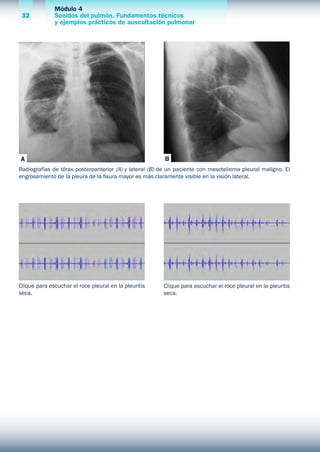

Radiografías de tórax posteroanterior (A) y lateral (B) de un paciente con mesotelioma pleural maligno. El

engrosamiento de la pleura de la fisura mayor es más claramente visible en la visión lateral.

Clique para escuchar el roce pleural en la pleuritis

seca.